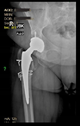

The guiding wire was inserted and controlled with fluoroscopy flashes (Figure 4). The drilling and reaming were carried out in accordance with the recommendations:

Figure 4.

The biocompatible aiming device after insertion of the guiding wire.

The direction of the cup stem was determined by the guide wire. The aiming device was needed to introduce this wire. After removing the aiming device, the next step was the drilling. Since a cannulated drill bit was used, the previously installed wire could guide the process. A self-positioning reaming tool was then used in the drilled channel. In the prepared cavity, the cup was fitted perfectly. Of the two stemmed cups available to us, the McMinn cup (Waldemar Link, Hamburg, Germany) had the simpler geometry and was therefore chosen. The stemmed cup was inserted according to the manufacturer’s recommendation. In the presence of a significant bone defect, a synthetic bone graft may be impacted for substitution.

The radiological examination allowed us to verify the close bone-to-implant contact and the unchanged position of the implant during follow-up.

In all the cases operated with the above-described targeting procedure, the stems of the cups remained between the cortical bone surfaces without perforation of the linea terminalis, as shown by postoperative radiographs. There were no complicated surgical situations. In 16 cases, the wound healings were uneventful, and the hips were able to bear weight again after postoperative rehabilitation.